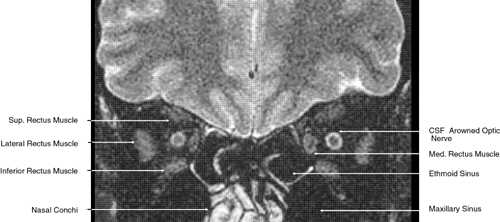

Fig. 17. Coronal images through anterior orbit. A. Computed tomography scan. B. T1-weighted magnetic resonance imaging.

Fig. 18. Coronal images through midglobe. A. Computed tomography scan. B. T1-weighted magnetic resonance imaging.

Fig. 19. Coronal images through midorbit posterior to the globe. A. Computed tomography scan.B. T1-weighted magnetic resonance imaging.